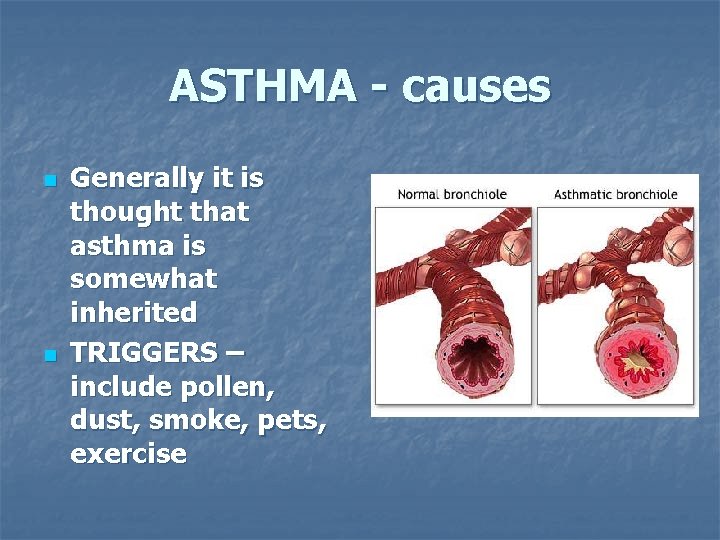

ASTHMA - causes n n Generally it is thought that asthma is somewhat inherited TRIGGERS – include pollen, dust, smoke, pets, exercise